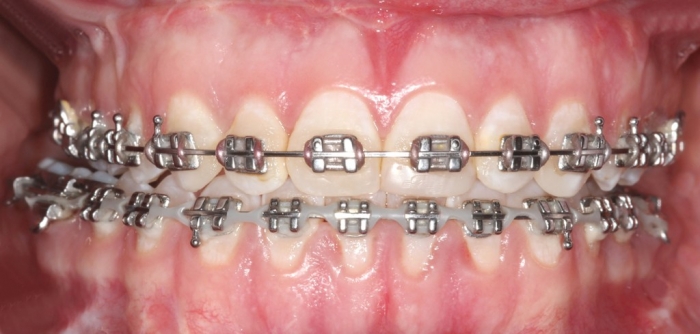

Mordida após a cirurgia - Clínica Cliniface

Mordida após a cirurgia